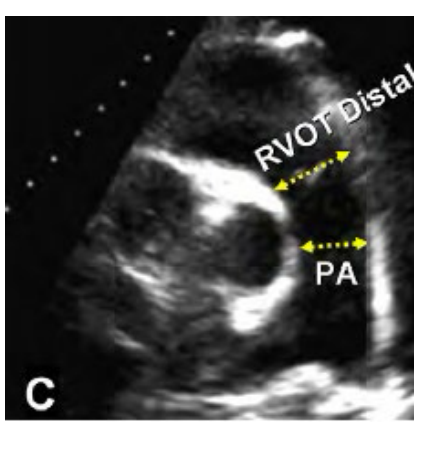

ow do you measure the RV diameter in PSAX at the great vessel view Distal, whats the abnormal diameter number?

RVOT distal diameter measured at end diastole. Inner edge to inner edge just proximal to the pulmonic valve

Abnormal is a Diameter > 2.5 cm

How is the main Pulmonary artery measured and what is the abnormal number?

Main Pulmonary artery is measured inner edge to inner edge at end diastole at the mid point.

Abnormal is > 2.0 cm